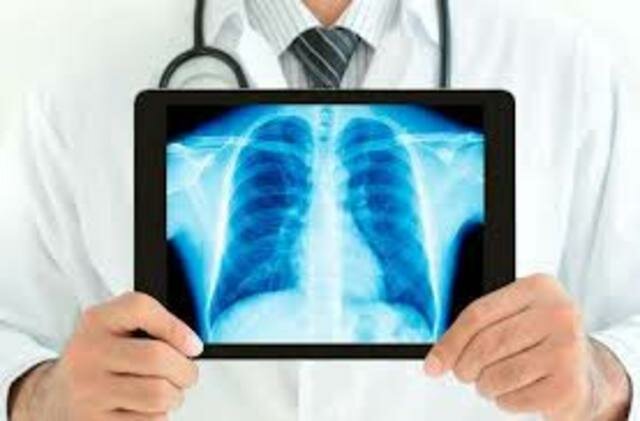

• Se comienza a utilizar habitualmente los rayos X en el diagnóstico por ultrasonido.

Se comienza a utilizar habitualmente los rayos X en el diagnóstico por ultrasonido.

Los médicos podían encontrar anomalías en el paciente de forma temprana y era muy beneficioso en la salud.